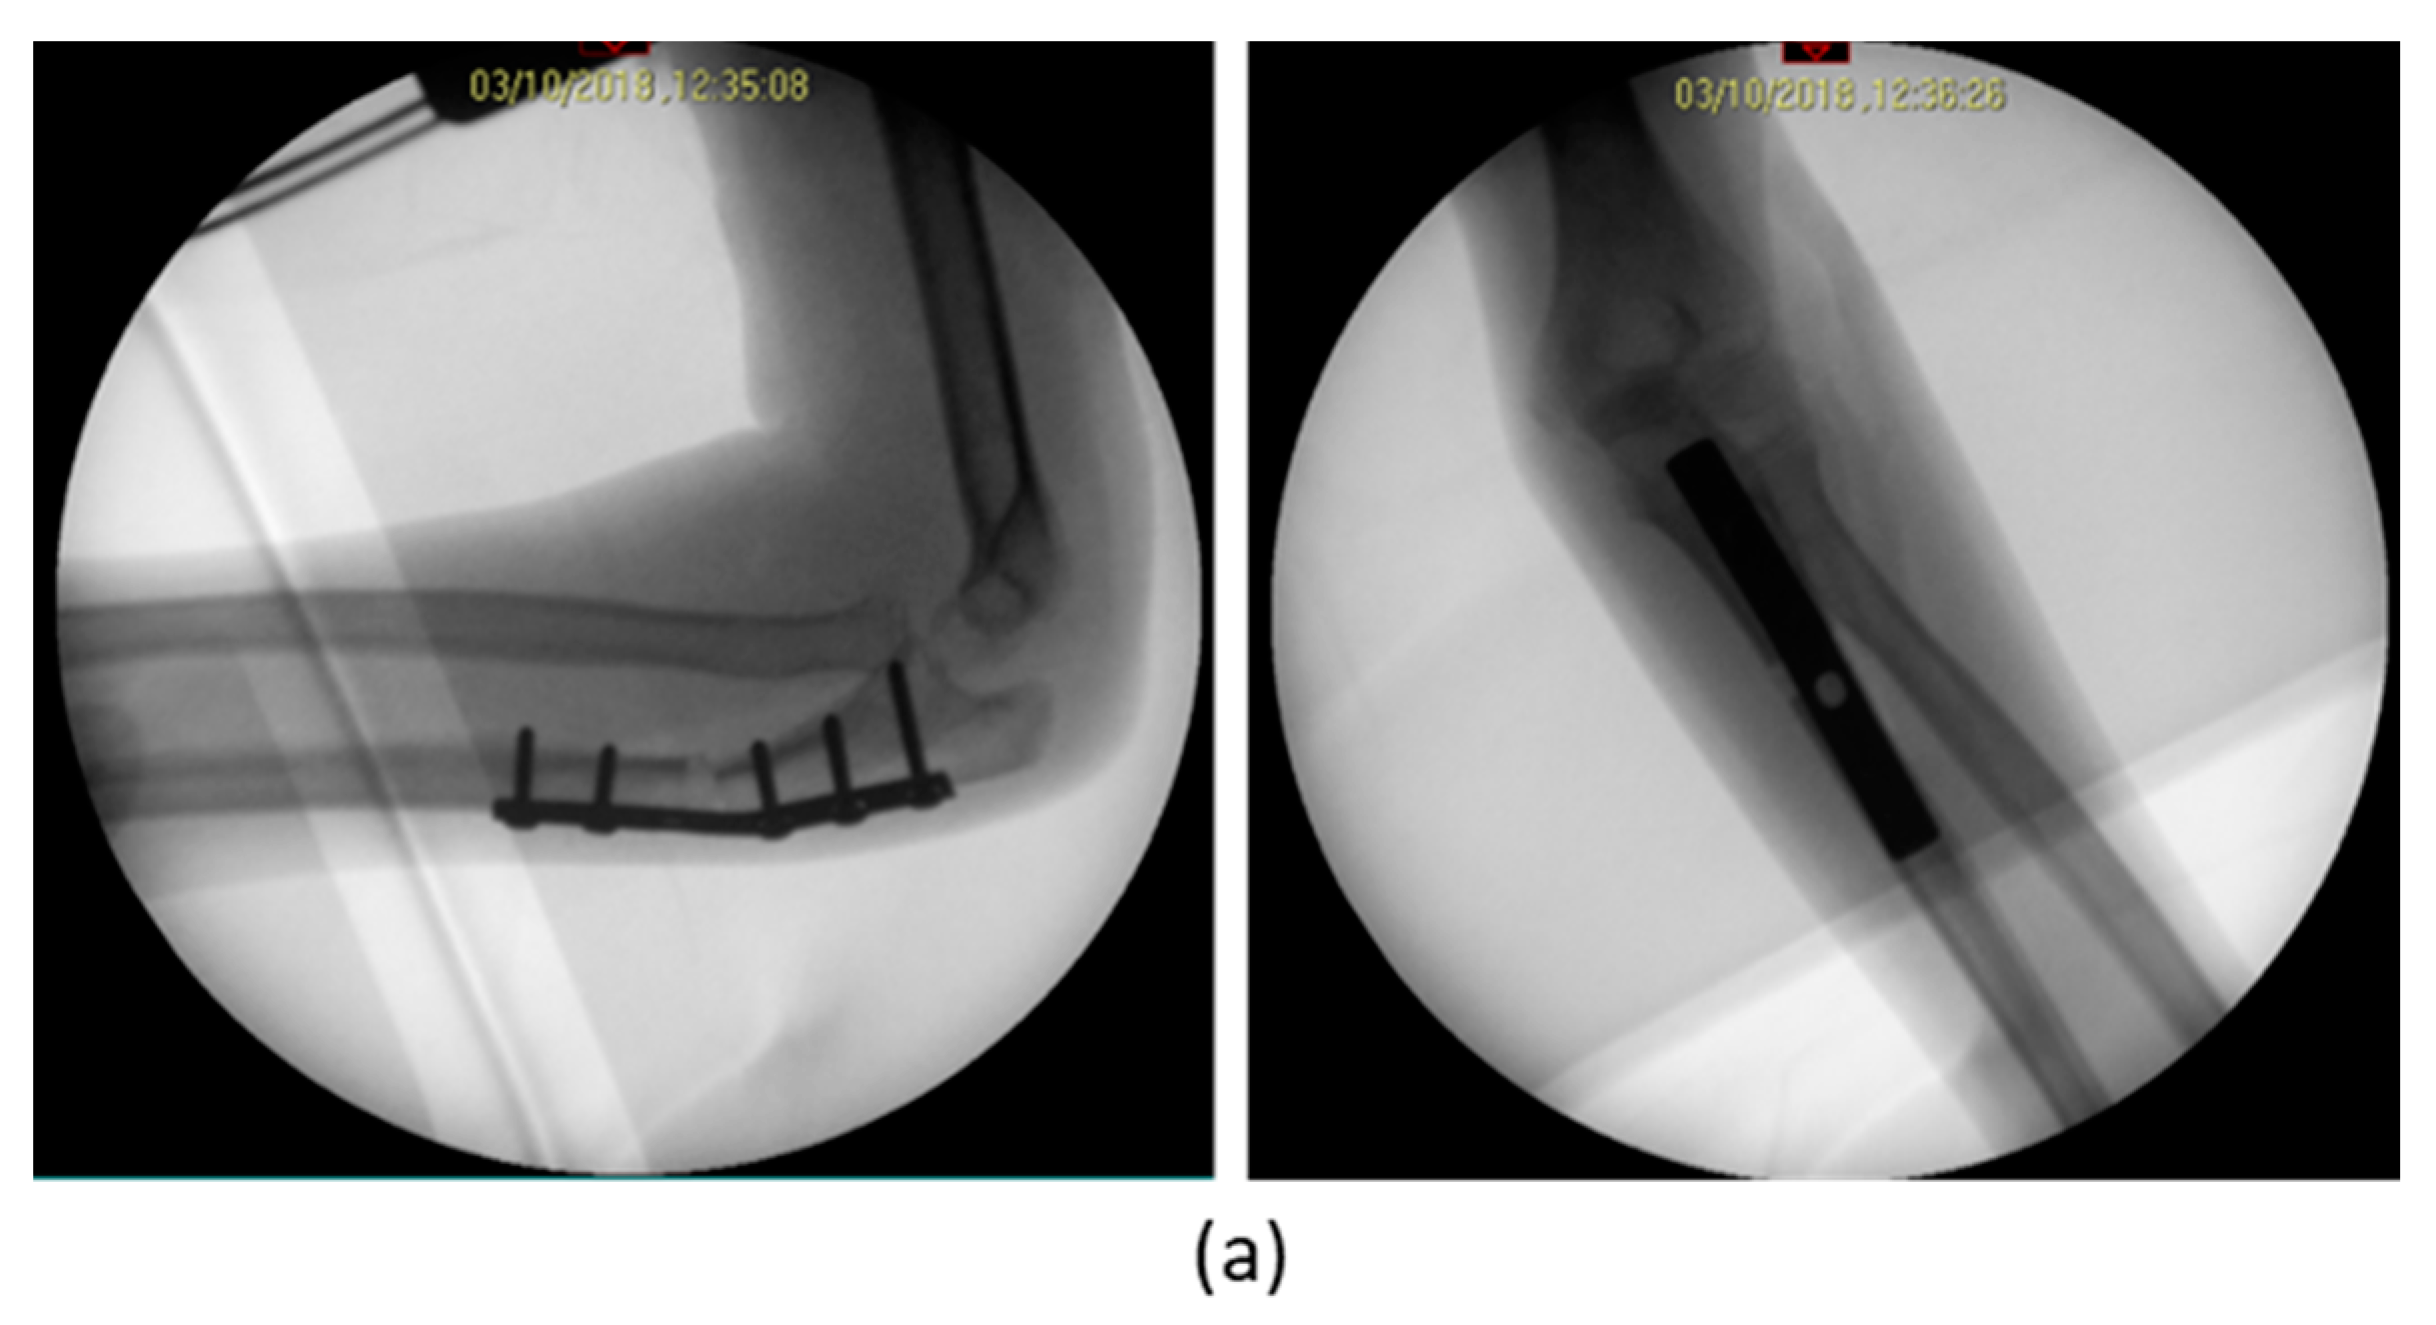

| 1 | F, 9 | Missed Monteggia Lesion | Post-traumatic | Proximal ulnar osteotomy stabilized with a 6-holes plate | None | Corrected |

| 2 | M, 13 | Focal fibrocartilagineous dysplasia | Congenital | Bifocal osteotomy stabilized with external fixator | Heterotopic bone formations | Fair (residual dislocation of the radial head with shortening of the ulna) |

| 3 | M, 15 | Post-traumatic forearm malunion deformity | Post-traumatic | Bifocal osteotomy stabilized with 1/3 tubular plate | None | Corrected |